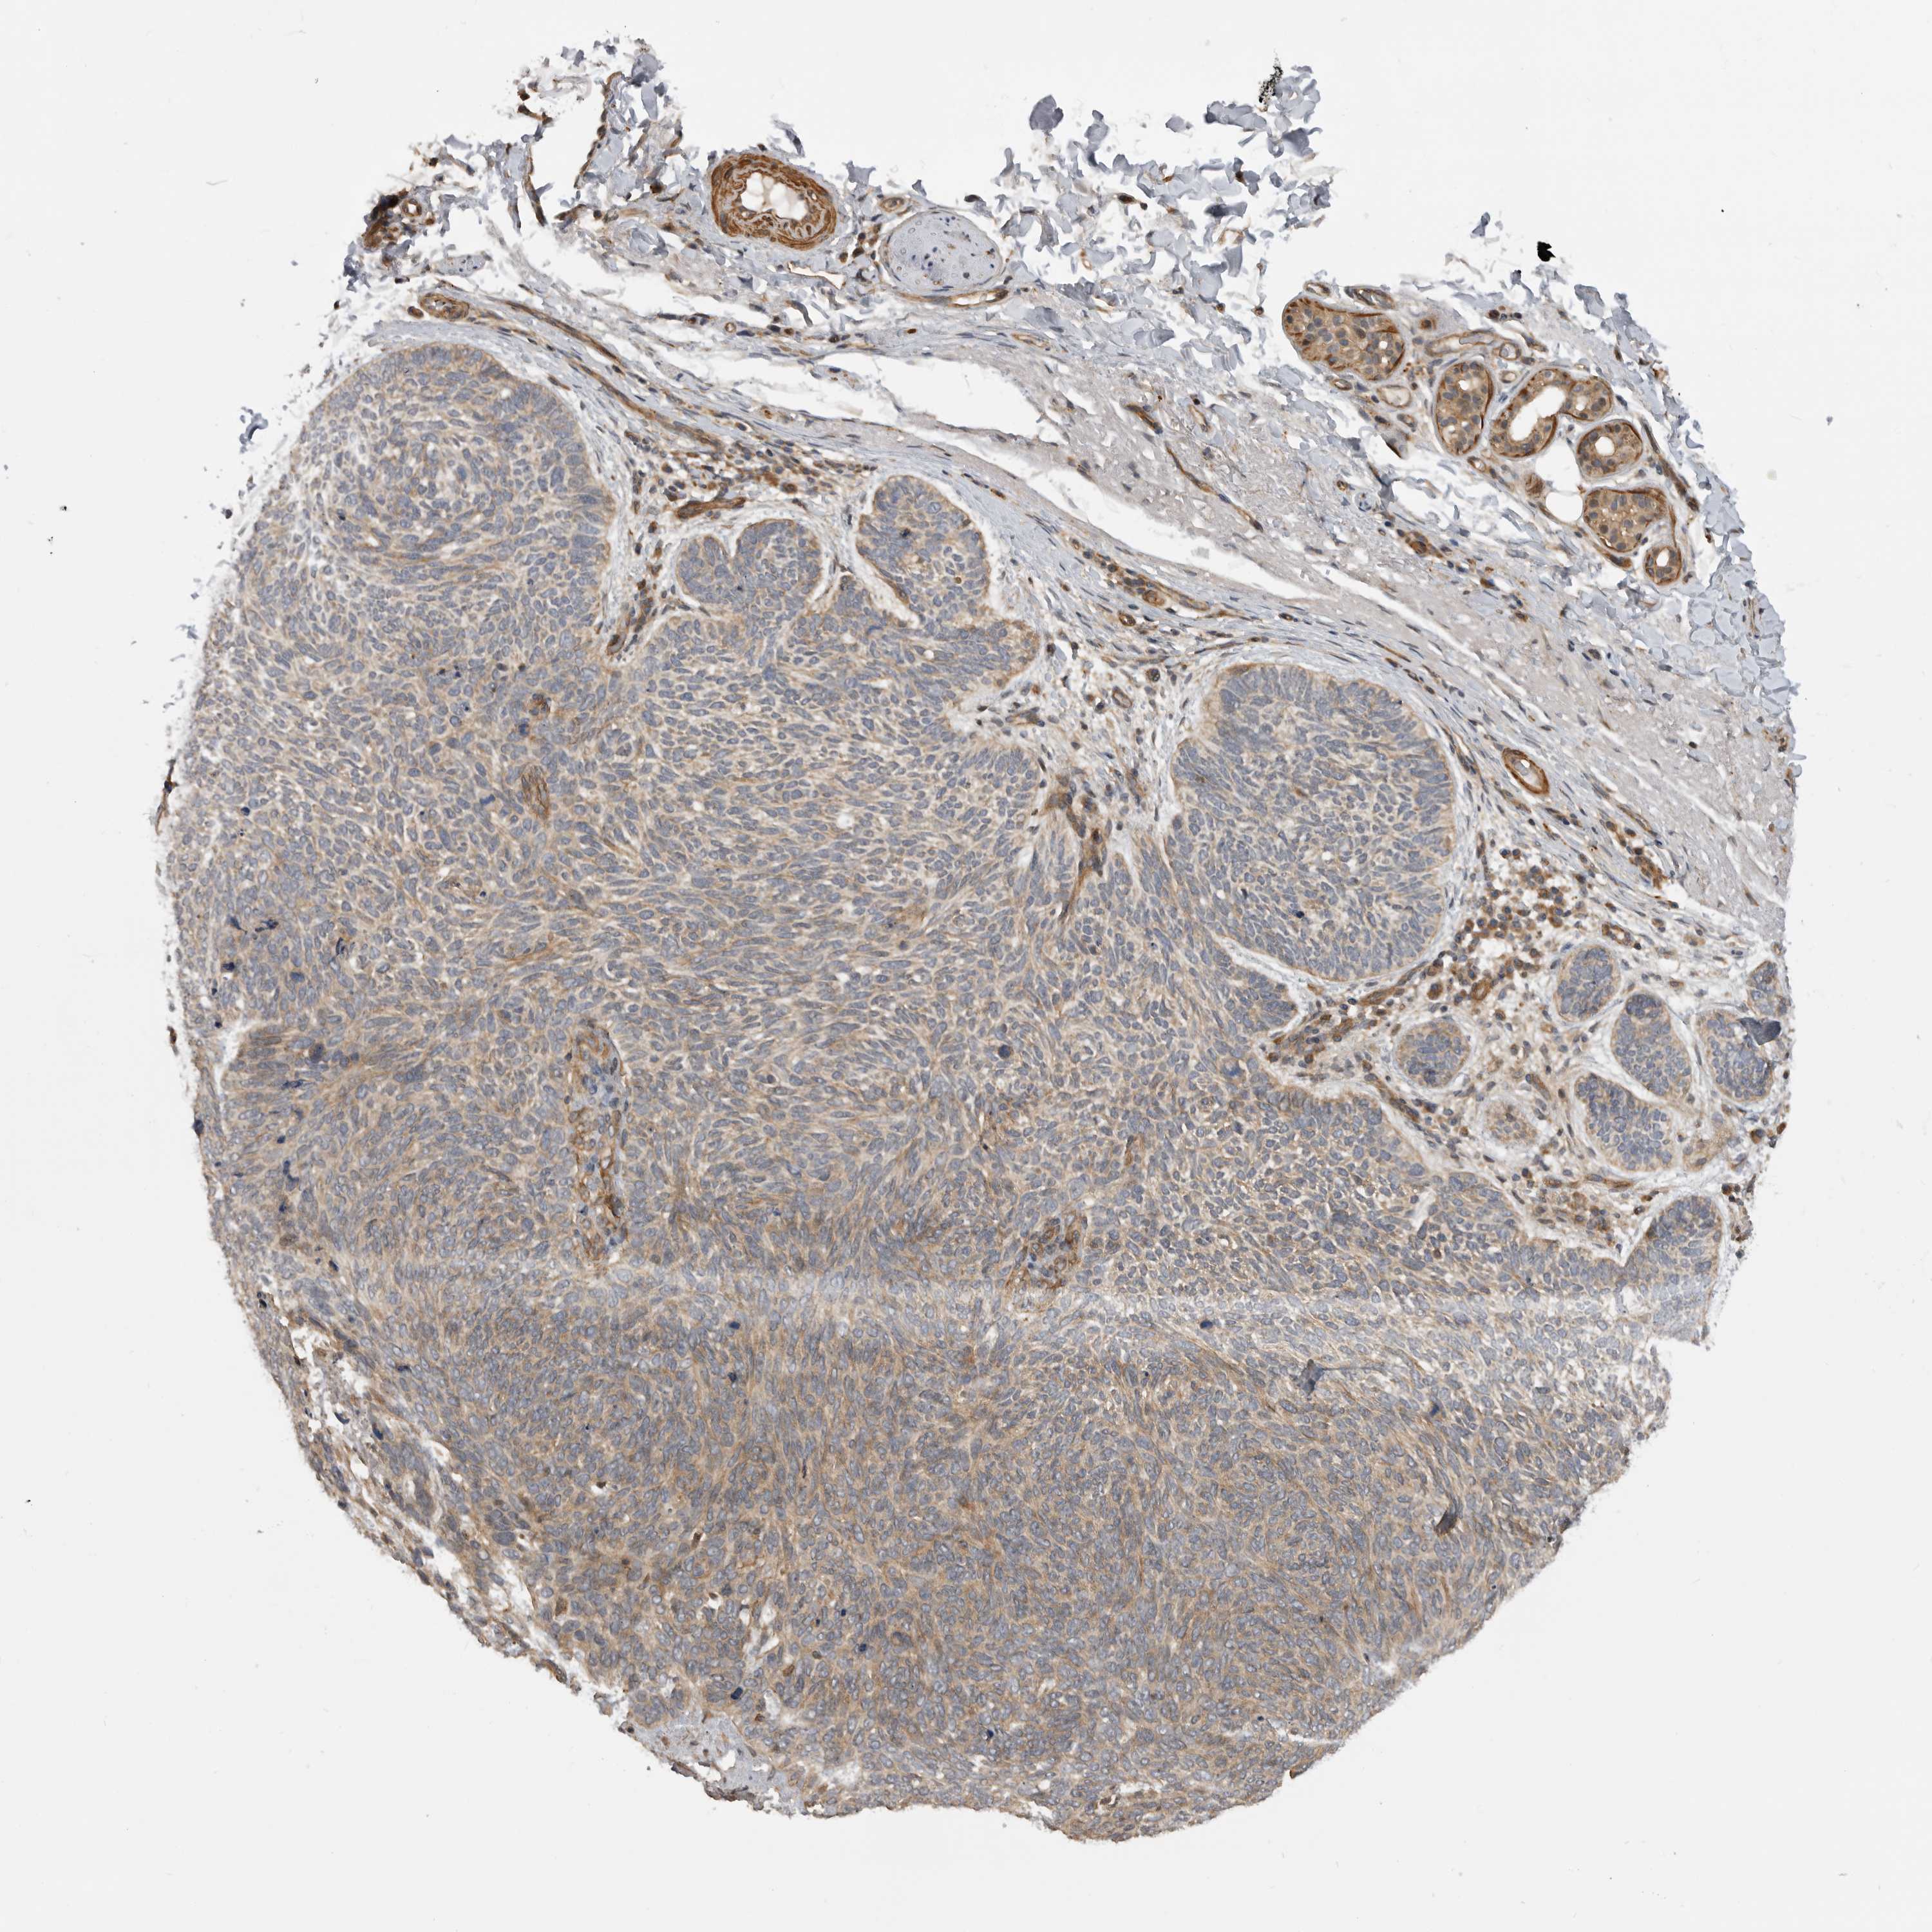

CANCER SKIN CANCER Show tissue menu

Basal cell and squamous cell cancer

SKIN CANCER - Protein expressioni

A mouse-over function shows sample information and annotation data. Click on an image to view it in a full screen mode. Samples can be filtered based on level of antibody staining by selecting one or several of the following categories: high, medium, low and not detected. The assay and annotation is described here.

Each image is clickable and will lead to virtual microscopy that enables deeper exploration of all samples and also displays staining intensity scores, fraction scores and subcellular localization as well as patient and tissue information for each sample.

Antibody HPA024358

Staining

High

Medium

Low

Not detected

Intensity

Strong

Moderate

Weak

Negative

Quantity

>75%

75%-25%

<25%

None

Location

Nuclear

Cytoplasmic/membranous

Cytoplasmic/membranous,nuclear

Basal cell carcinoma

Squamous cell carcinoma, NOS

Squamous cell carcinoma, metastatic, NOS